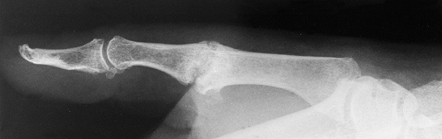

While ligament reconstruction and soft-tissue procedures are usually

preferred, in the arthritic thumb MCP joint, arthrodesis (Fig. 72.1, Fig. 72.2) provides a more lasting option and is generally preferred to arthroplastic techniques for a number of different disorders (36).

Figure 72.1. Thumb metacarpophalangeal joint fusion, anteroposterior view.